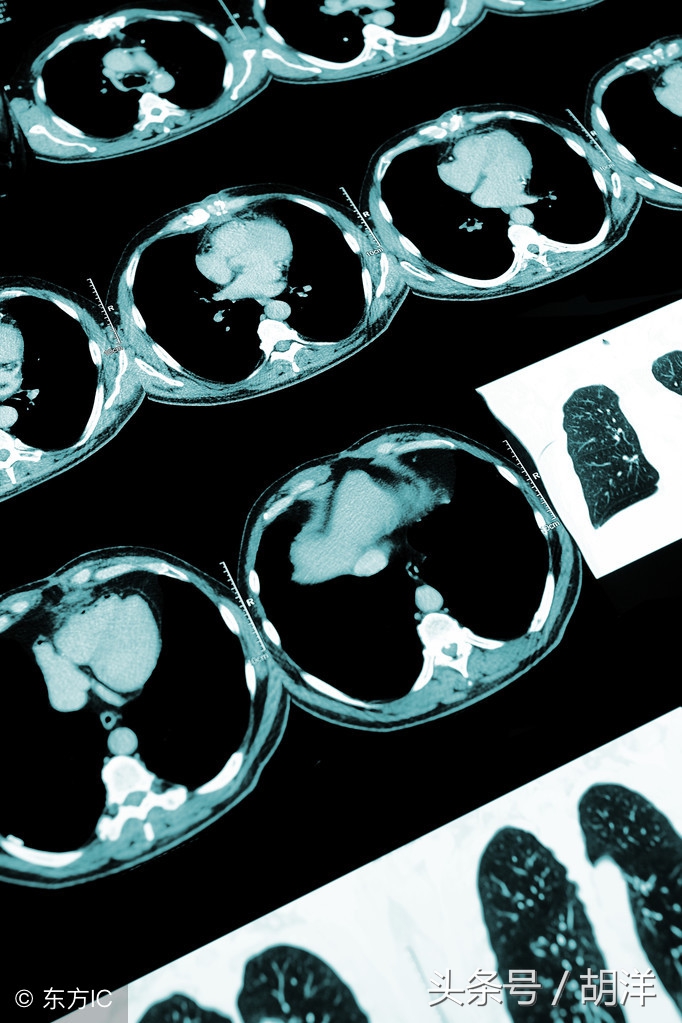

其实任意哪个季节痰中带血都是需要重视的,像我们很多人所担心的CT发现不了的肺部问题存不存在呢,理论上是存在的,但其实几率非常低,肺部的疾病即使是气管内的问题在胸部CT上都会有提示,我们胸部CT可以发现肺内所有超过1mm大小的病灶结节,而小于1cm以下的结节大部分是不会出现任何症状的,痰血的情况可以说更加罕见。